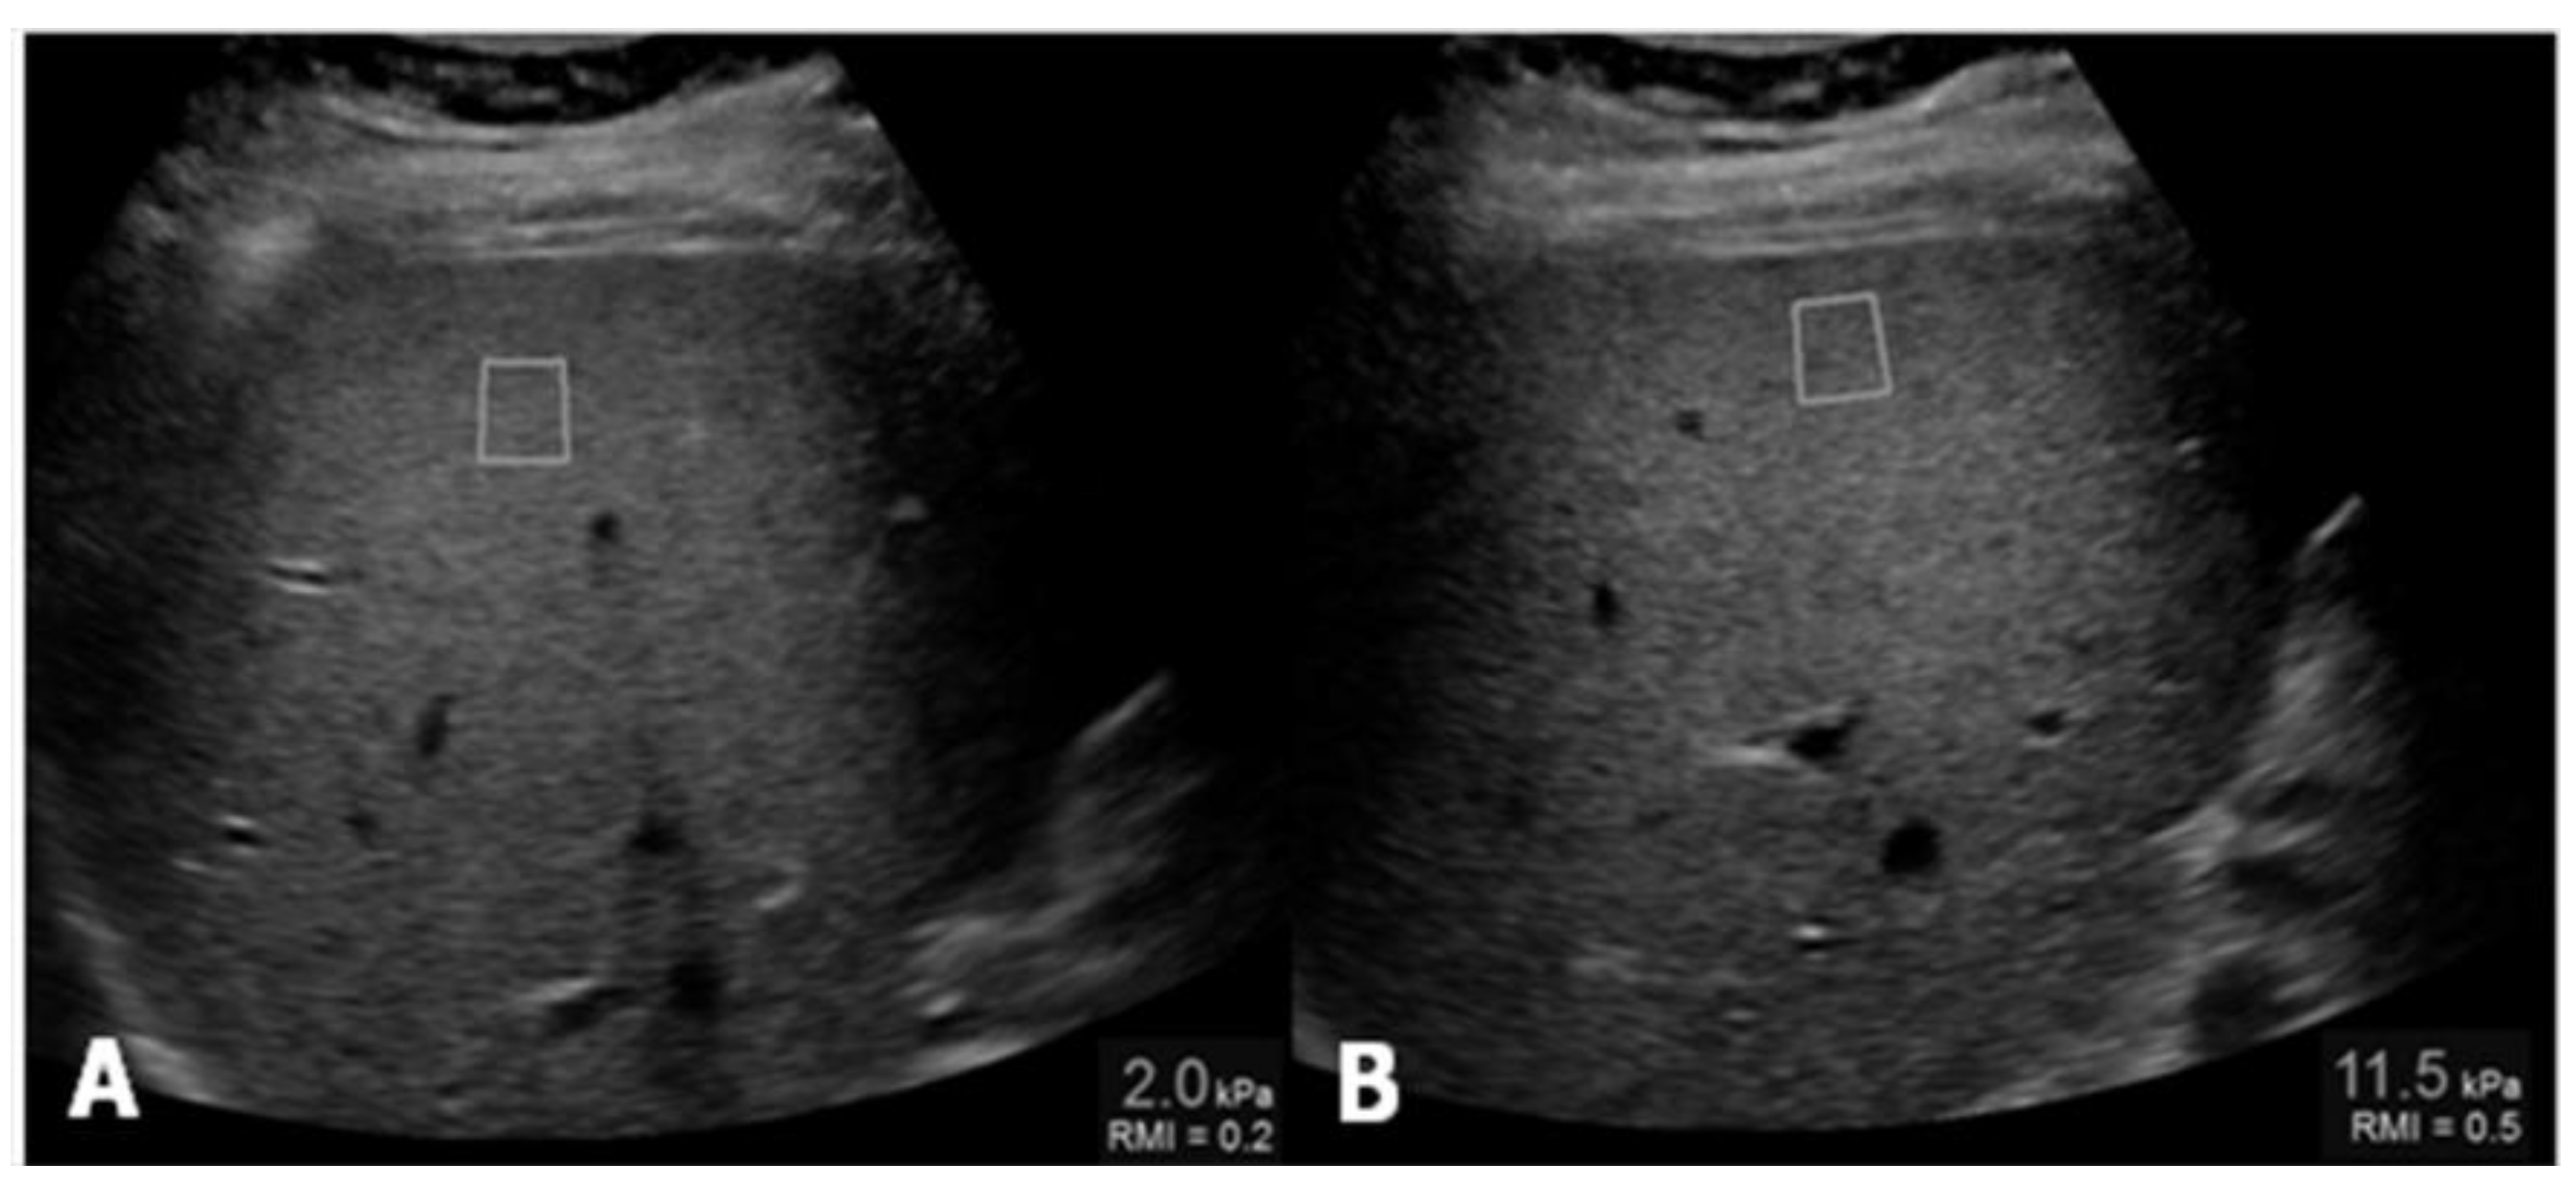

Controlled attenuation parameter (CAP) has been proposed as a non-invasive method for the determination and measurement of hepatic steatosis. The mechanism of CAP is the reduction in amplitude of ultrasound that can be estimated as it is amplified through the liver tissue. This procedure uses the same radio-frequency data used for estimation of liver stiffness with Fibroscan (Echosens, Paris, France), an ultrasound-based vibration-controlled transient elastography device [12], comparing shear stiffness to that of a normal liver, which is between 6.5 and 7 kPa (Figure 2).

Figure 2.

(A) Measurement of liver stiffness shows an estimated Young’s modulus of 2.0 kPa, below the cut-off for the diagnosis of stage F1 fibrosis; (B) Measurement of liver stiffness shows an estimated Young’s modulus of 11.5 kPa which reveals the presence of fibrosis.